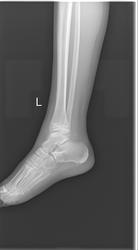

Здравствуйте. Посмотрите пожалуйста снимки, девлчке 8 лет. Что вы думаете по этому поводу? нет ли тут подвывиха?

Всё же для поиска подвывиха нужна строго боковая проекция.

Неоднозначно всё